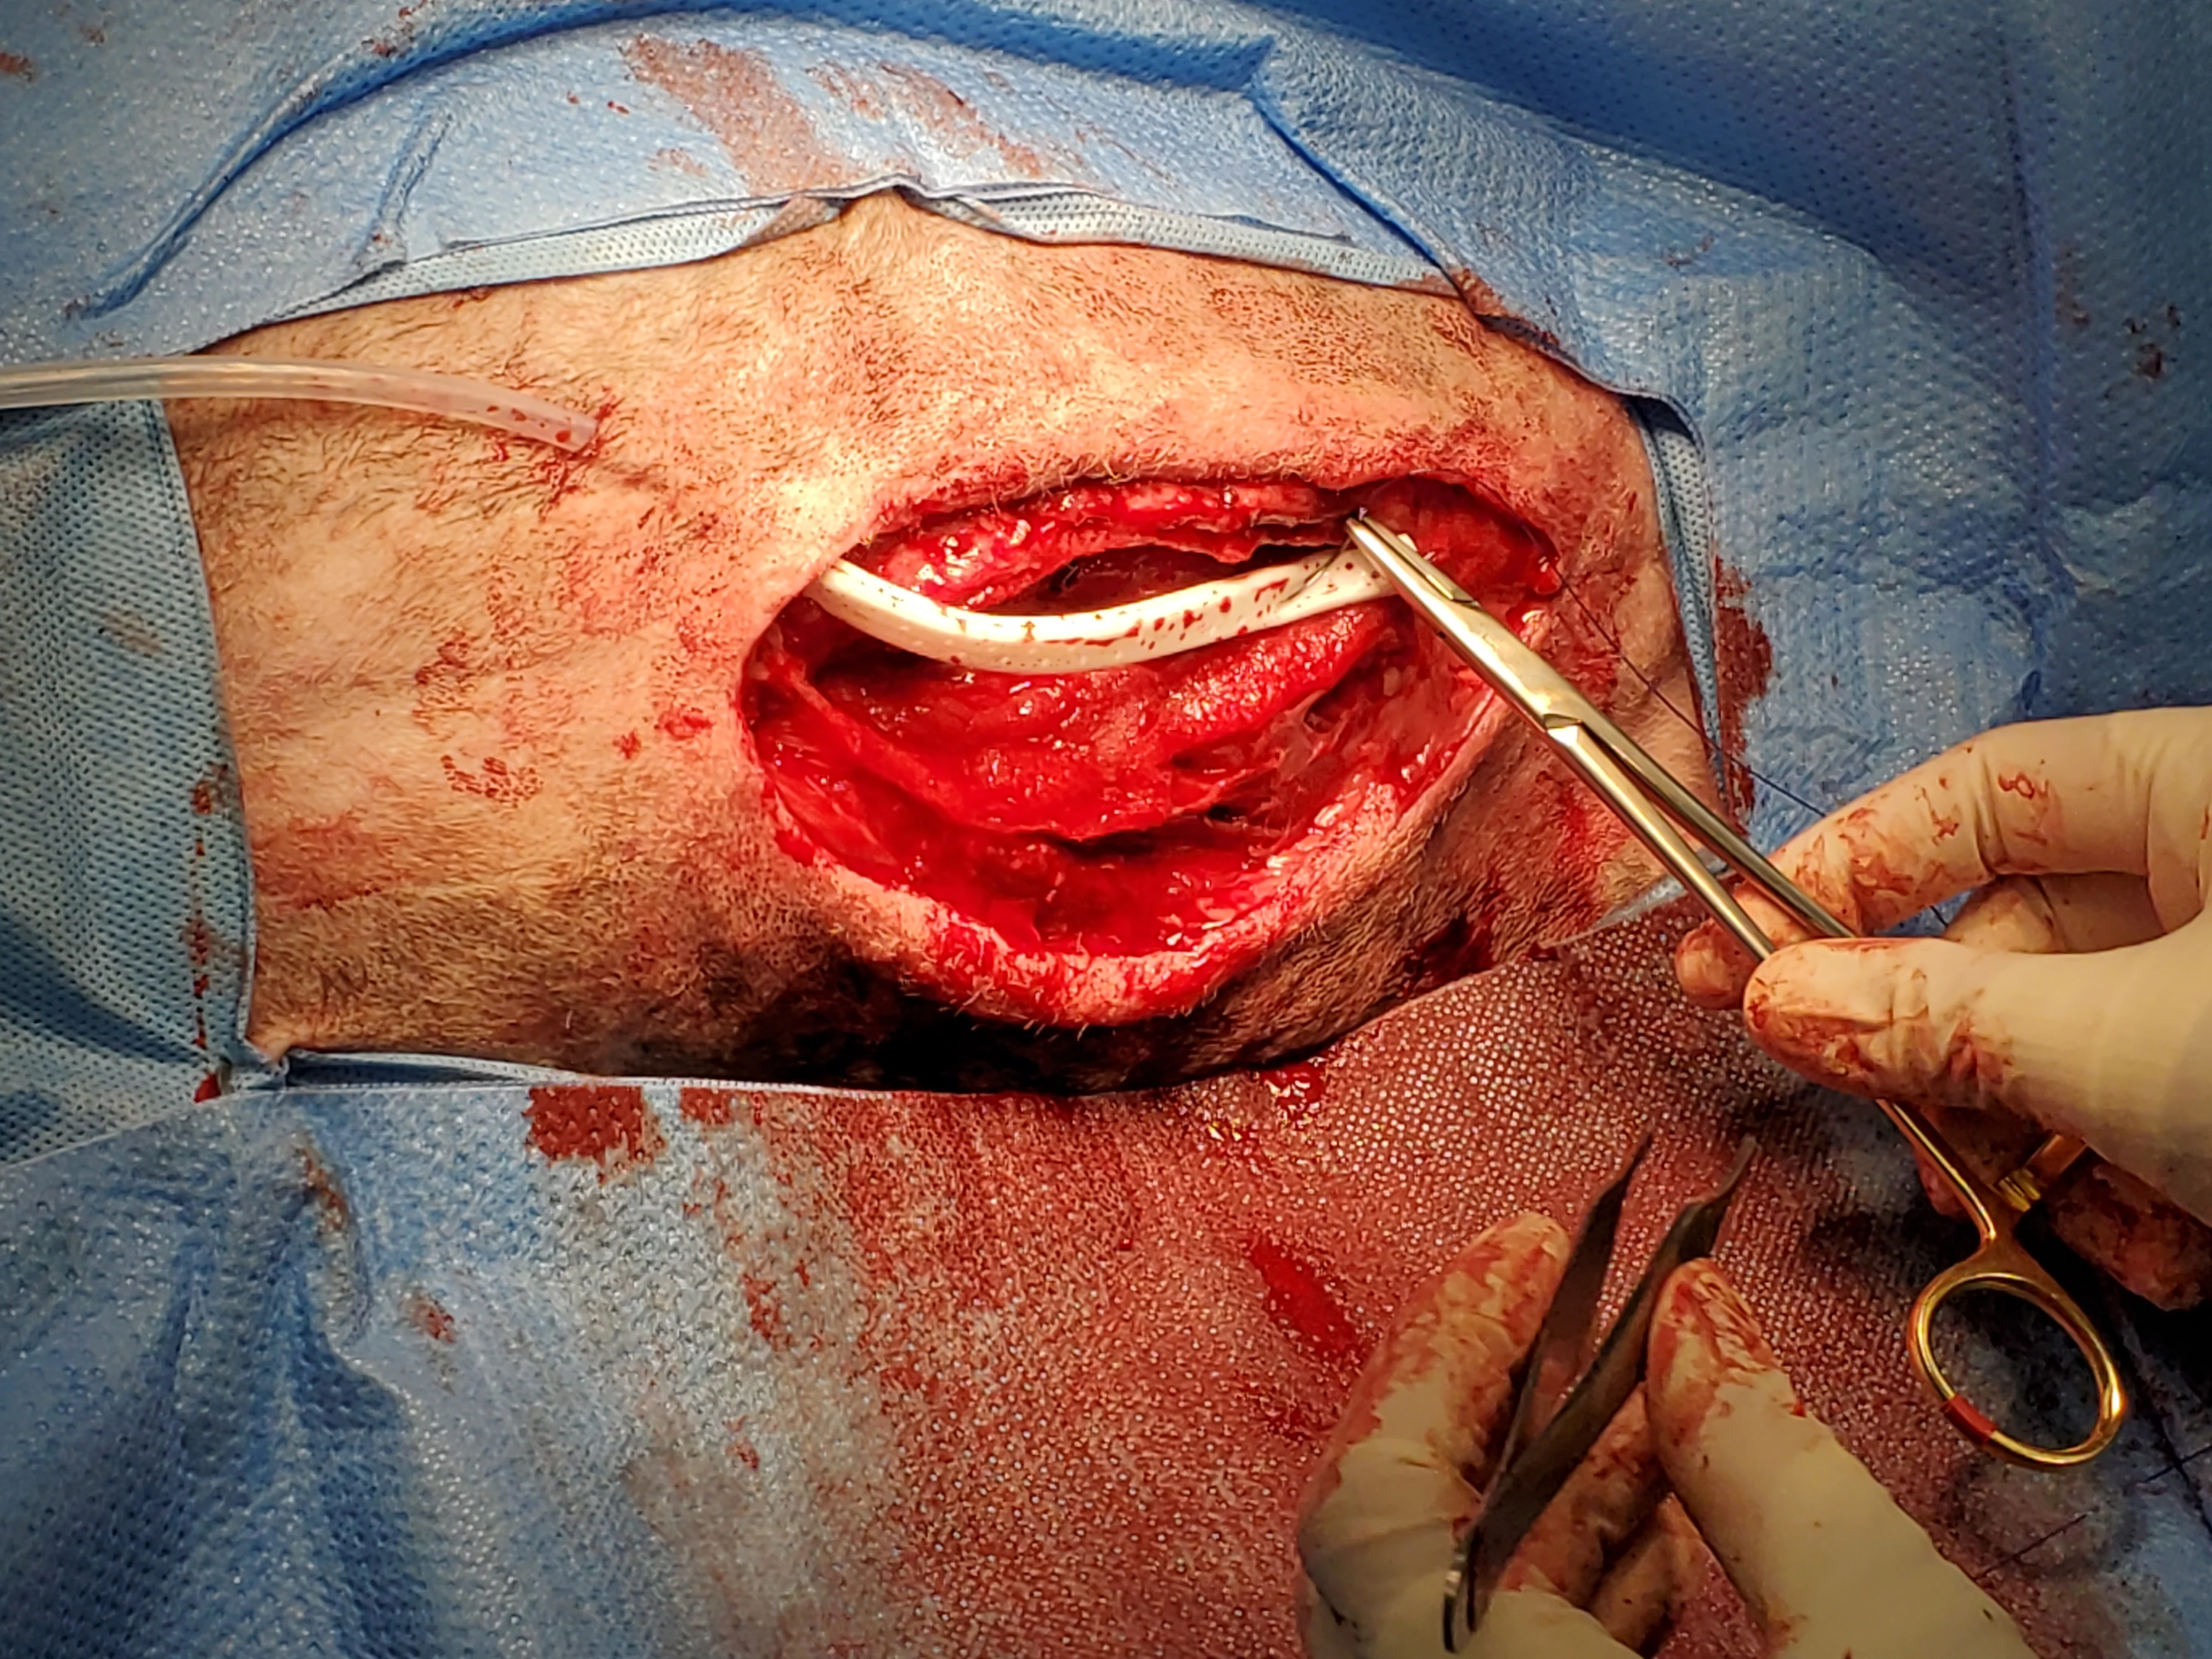

Figure 11 Negative pressure wound therapy (NPWT) was applied because of the wound location. Wounds treated with NPWT close more quickly than those treated with other traditional modalities. In this patient, NPWT would also maintain negative thoracic pressure if the sternal closure failed.22 Antibiotics were changed to chloramphenicol (47.5 mg/kg PO every 8 hours) based on in vitro susceptibilities and clinical effectiveness of this antimicrobial.23 In the authors’ experience, wounds infected with resistant Staphylococcus spp typically respond to systemic aminoglycosides or chloramphenicol in the veterinary setting.

Figure 12 With the patient under anesthesia, the foam sponge was removed and the wound inspected every 2 to 3 days. Longer application of NPWT may result in granulation tissue ingrowth into the foam block.22 After 4 days of NPWT and antibiotic administration, cellulitis resolved, granulation tissue started to form near the wound margins, and a tissue culture was negative for S aureus but had a moderate growth of S marcescens with good susceptibility to trimethoprim sulfa but only intermediate susceptibility to chloramphenicol. Antimicrobial treatment was switched to trimethoprim sulfa (12.9 mg/kg PO every 12 hours).